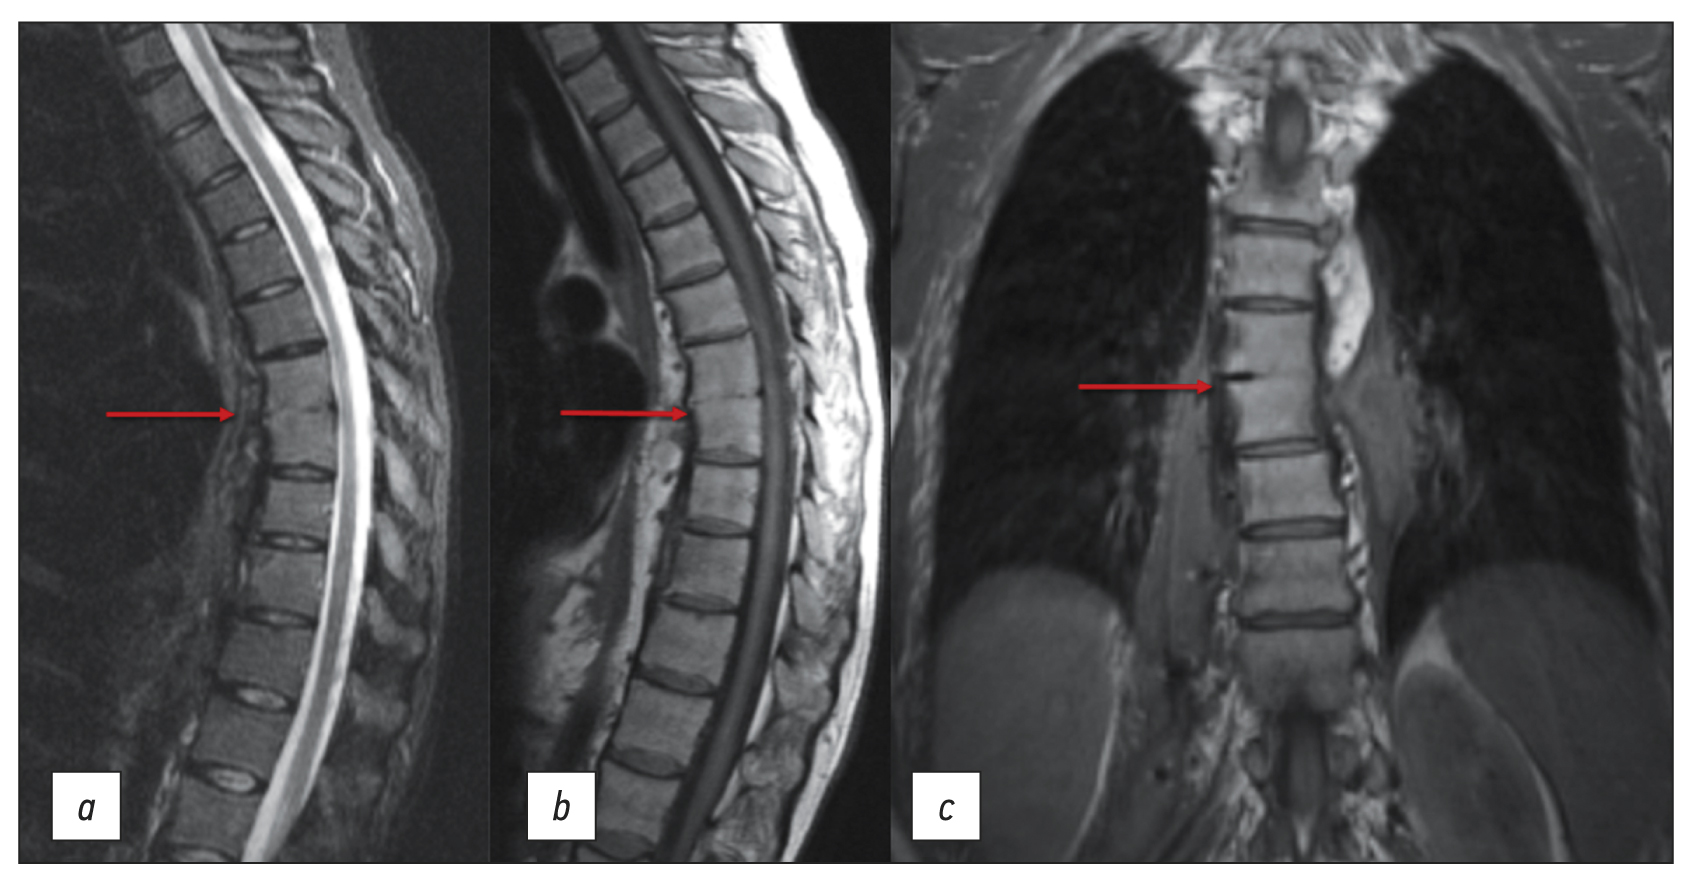

Frequency of various cardiac complications in children with repaired tetralogy of Fallot identified by computer tomography

BACKGROUND: Tetralogy of Fallot represents 7–10% of all cases of congenital heart disease, as it occurs in approximately 0.5 per 1,000 live births and is the second most common form of complex congenital heart disease. Advances in diagnosis, surgical techniques, and postoperative treatment have led to an increasing number of patients reaching adulthood, with a dramatic increase in the survival rate to almost 90% at 30 years, thereby creating a need for long-term monitoring of certain anatomic parameters to identify complications in a timely manner. This study aimed to investigate the frequency of computed tomography detected complications after radical correction of Tetralogy of Fallot in pediatric patients.

AIM: to identify markers between the most frequency computed tomography detected complications after repair of Tetralogy of Fallot in pediatric patients.

MATERIALS AND METHODS: A retrospective analysis was conducted on 613 patients with Tetralogy of Fallot from October 2011 to June 2020. The study included a total of 116 patients (69 men and 47 women) who experienced complications after a repair of Tetralogy of Fallot, as identified by computed tomography. At the time of repair of Tetralogy of Fallot, the patient’s average age ranged from 10 to 36 months (mean: 12 months), average body weight was 21 kg, average height was 105.4 cm, and average body surface area was 0.74 m2. The patients’ median age at the time of the computed tomography examination was 17.5 years (age range: 7–36 years).

RESULTS: Among the 116 patients who exhibited complications after an repair of Tetralogy of Fallot, 49 had a pulmonary artery stenosis, 92 had a pulmonary artery branch stenosis (56 of them of the left main pulmonary artery branch, and 36 of them of the right main pulmonary artery branch), 8 had a right ventricular outflow tract stenosis, 32 had a ventricular septal defect, 1 had a shunt thrombosis, 12 had a postoperative deformation of the pulmonary artery, 10 exhibited a marked right ventricular dilatation, 2 had an right ventricular outflow tract aneurysm, and 6 suffered from conduit calcification and stenosis. Moreover, patients with left main pulmonary artery branch stenosis had a 6.5 times greater chance of developing an right main pulmonary artery branch stenosis in (p <0.001).

CONCLUSION: The most frequently computed tomography detected complications after a repair of Tetralogy of Fallot were pulmonary artery stenosis and pulmonary artery branch stenosis. Patients with pulmonary artery stenosis and pulmonary artery branch stenosis exhibit no significant differences in terms of age, anthropometric parameters (height, weight, and body surface area), and gender distribution in the presence or absence of different stenosis types (pulmonary artery, right main pulmonary artery branch, or left main pulmonary artery branch). However, an right main pulmonary artery branch stenosis increases the chances of developing an left main pulmonary artery branch stenosis.